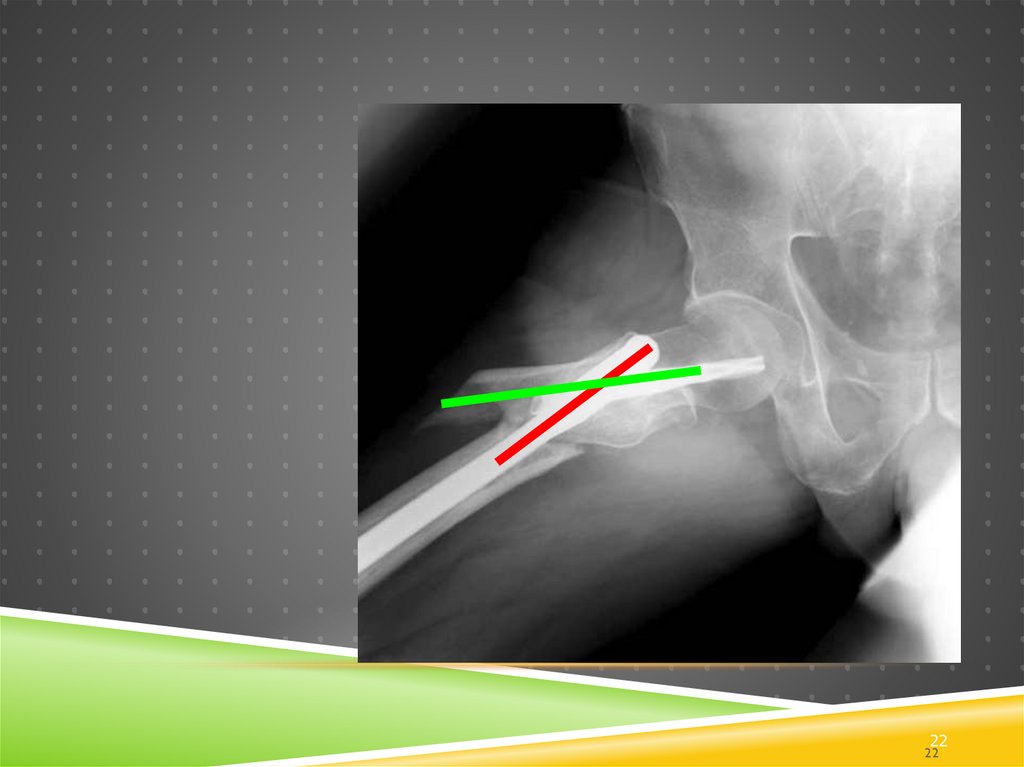

22.

22